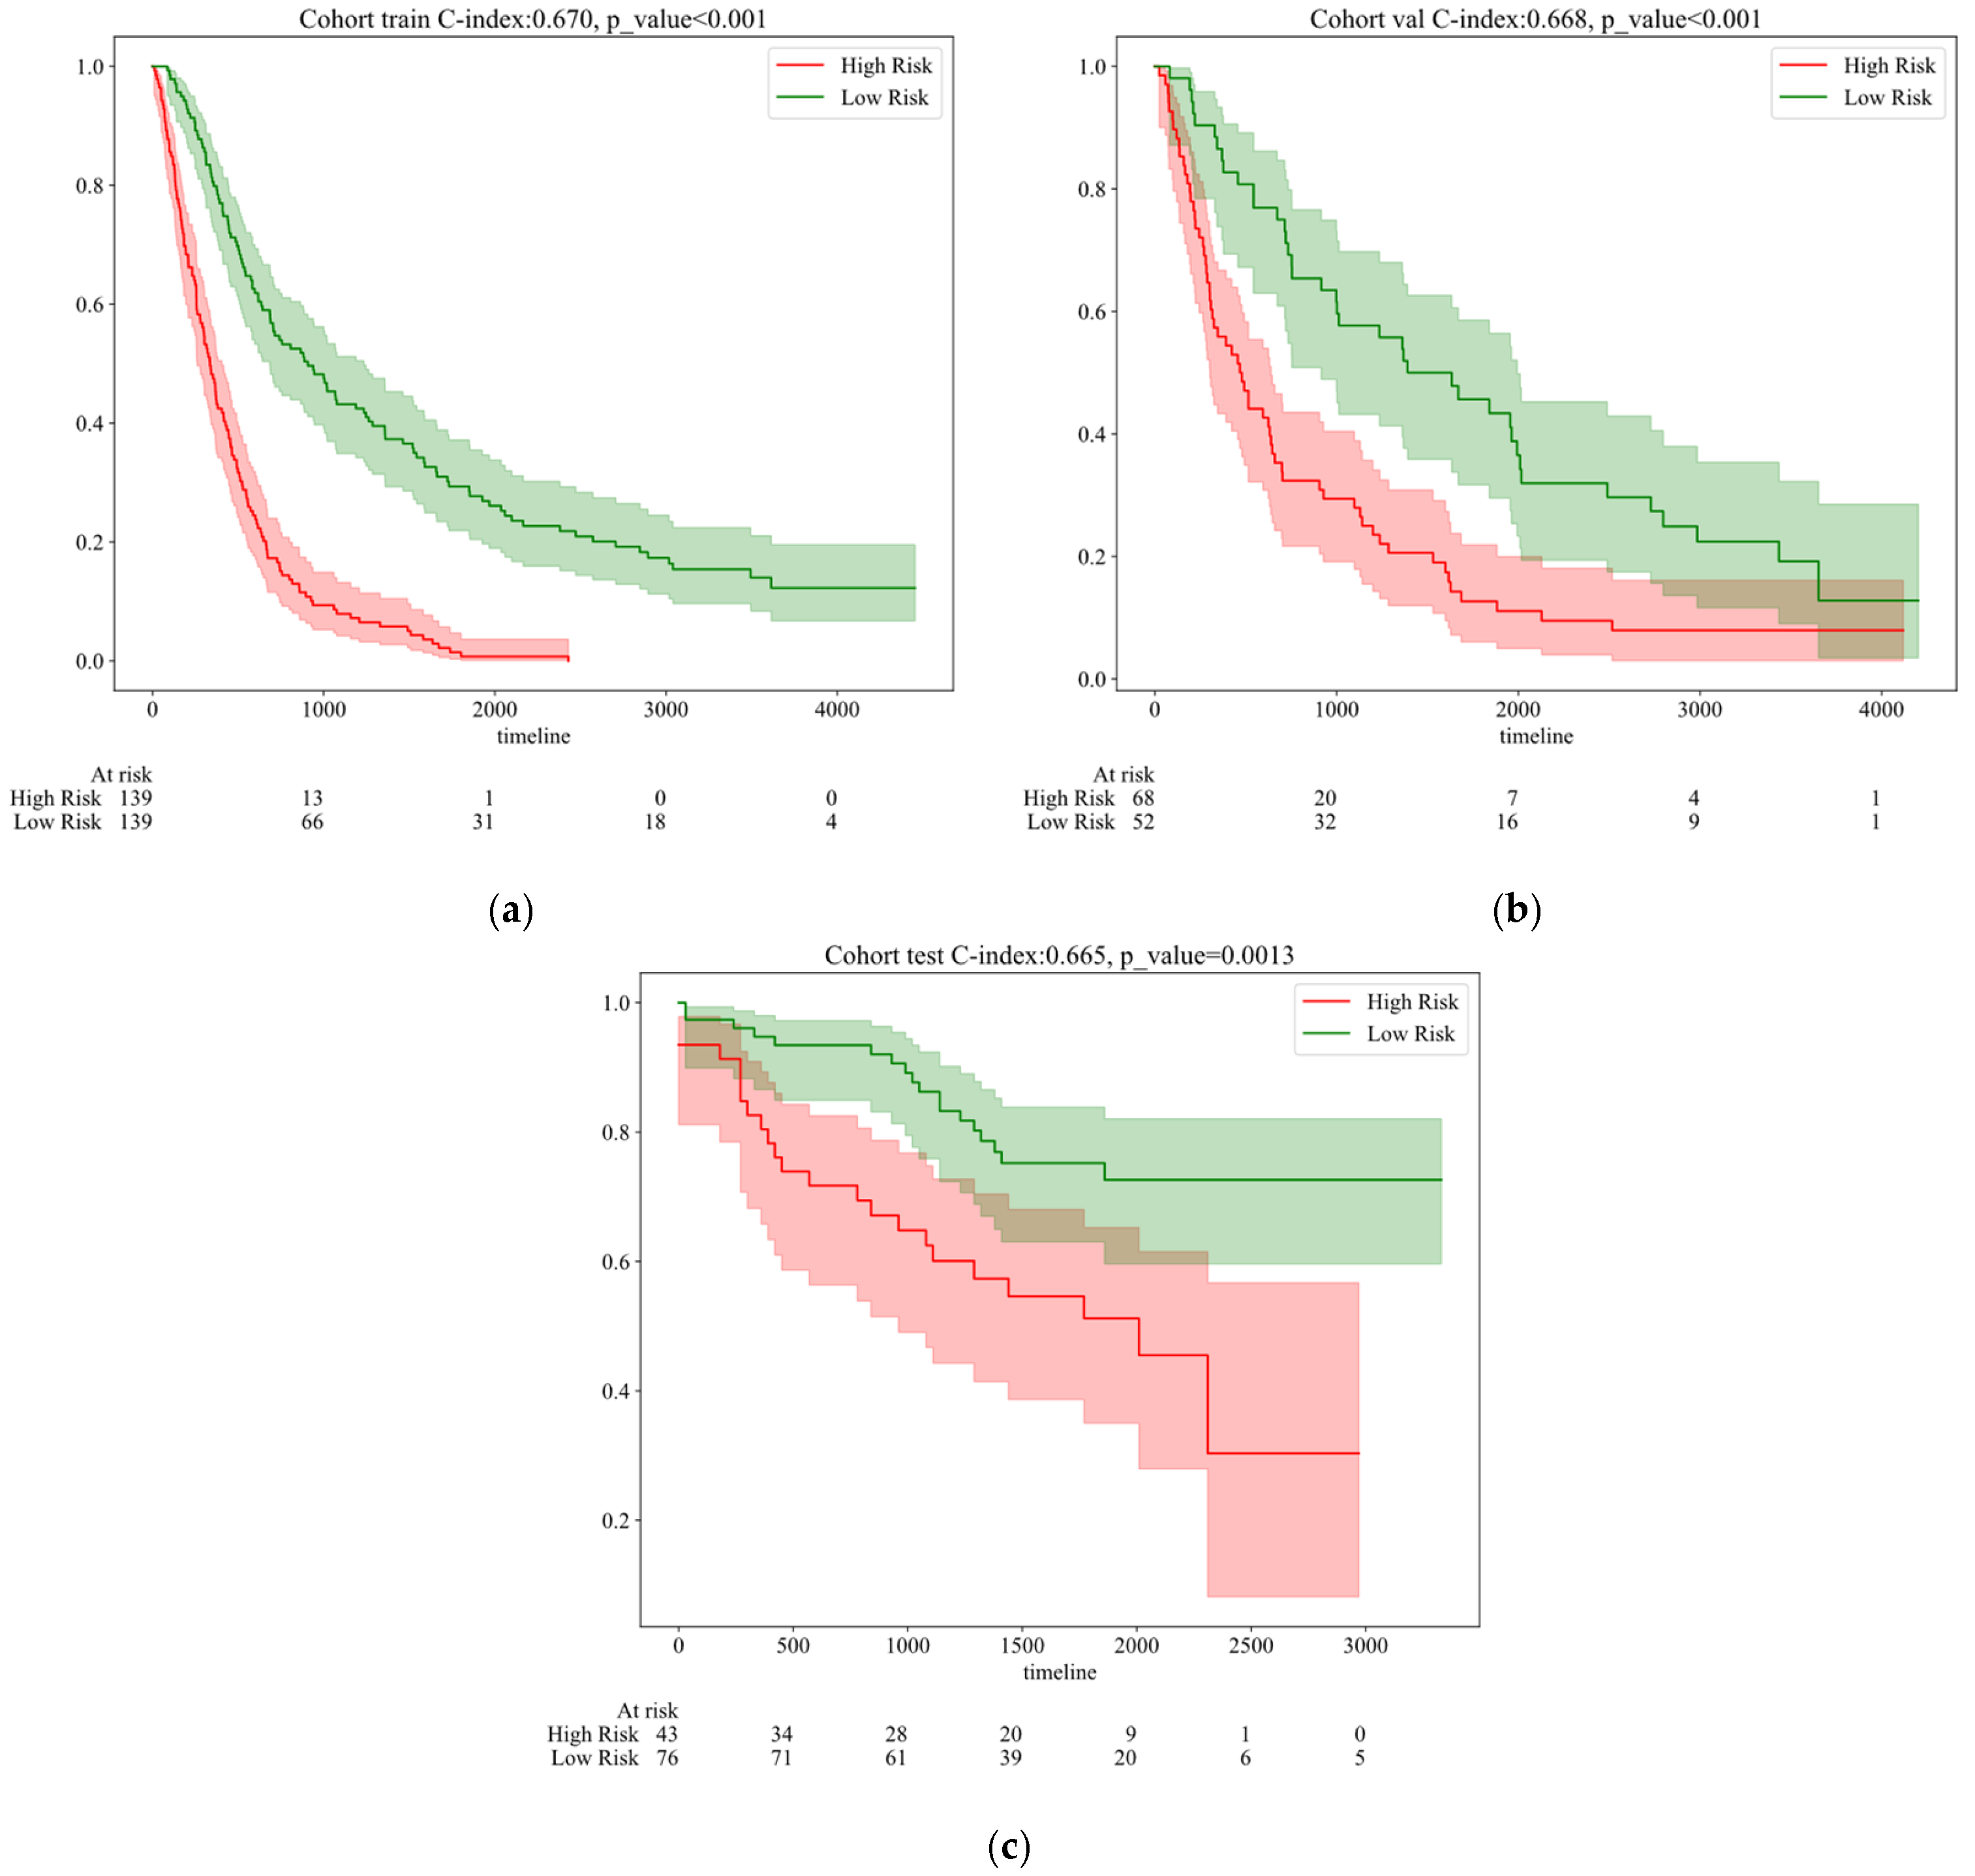

5.2. Survival Time Prediction